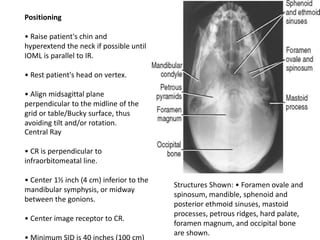

Positioning

• Raise patient's chin and

hyperextend the neck if possible until

IOML is parallel to IR.

• Rest patient's head on vertex.

• Align midsagittal plane

perpendicular to the midline of the

grid or table/Bucky surface, thus

avoiding tilt and/or rotation.

Central Ray

• CR is perpendicular to

infraorbitomeatal line.

• Center 1½ inch (4 cm) inferior to the

mandibular symphysis, or midway

between the gonions.

• Center image receptor to CR.

Structures Shown: • Foramen ovale and

spinosum, mandible, sphenoid and

posterior ethmoid sinuses, mastoid

processes, petrous ridges, hard palate,

foramen magnum, and occipital bone

are shown.